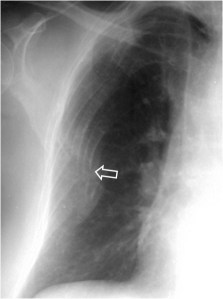

SIGNO DE LA CISURA INCOMPLETA, DE LA PSEUDOCAVIDAD O SIGNO DE LA ESPINA DE ROSA

Es un signo de derrame pleural en la cisura mayor visible en la radiografía de tórax, en un paciente con cisura mayor incompleta. Es más frecuente verlo en el lado derecho ya que en el izquierdo la silueta cardiaca puede ocultarlo.

La presencia de una zona radiotransparente perihiliar, circunscrita lateralmente por una línea curva bien marcada (flecha blanca), en cuya periferia se observan varios grados de opacidad, corresponde a la presencia de líquido en la cisura mayor incompleta. La línea curva termina en un extremo en punta (flecha roja), que estará más cercana al hilio cuanto más completa sea la cisura.

El nombre de pseudocavidad hace referencia a la radiolucencia perihiliar, mientras que el de espina de la rosa se refiere a la morfología de la opacidad, con el extremo en punta.